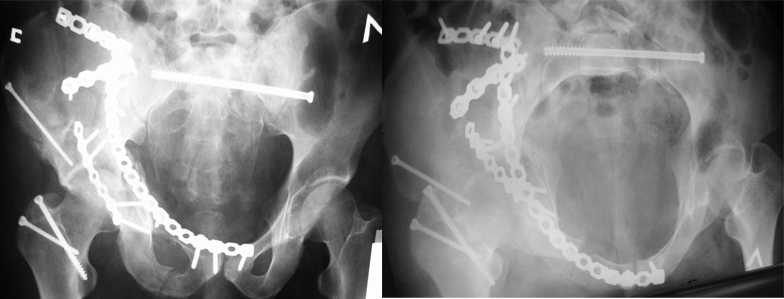

Уважаемые коллеги! С прошедшеми Вас праздниками. Теперь ближе к трудовым будням. Поступила 16 летняя девушка неделю назад. Механизм травмы падение с 5 этажа. Краткий диагноз:закрытый перелом левой ключицы, левого плеча, закрытый вертикально и ротационно нестабильный перелом костей таза:закрытый перелом левой подвздошной кости, переломы лонной кости справа, перелом обоих колонн вертлужной впадины слева;субкапитальный перелом шейки левой бедренной кости со смещением. По тактике лечения таза возникли следующие вопросы: 1. С чего начать - фиксации переломов вертлужной впадины или устранения деформаций таза? 2. Надо ли фиксировать шейку или фиксировать бедро в аппарате вместе с тазом, а после сращения таза планировать ТЭП ТБС? Если имеются еще какие подводные камни, будем рады выслушать.Спасибо.

На картинке подобный случай, только без шейки, сделано через месяц или полтора после травмы.